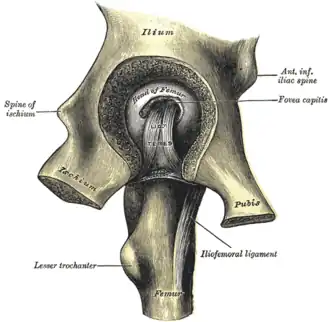

Capsule of hip-joint (distended). Posterior aspect. (Ilium labeled at top.) | |